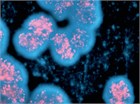

1. 神経芽腫の診断および治療は、小児腫瘍の診療に習熟した小児科医、小児外科医、病理医、放射線科医の協力のもとで行われるべきである(推奨度1)

1. 神経芽腫の予後因子として、病期分類、発症年齢、病理分類、腫瘍細胞の生物学的特性が重要である(推奨度1)